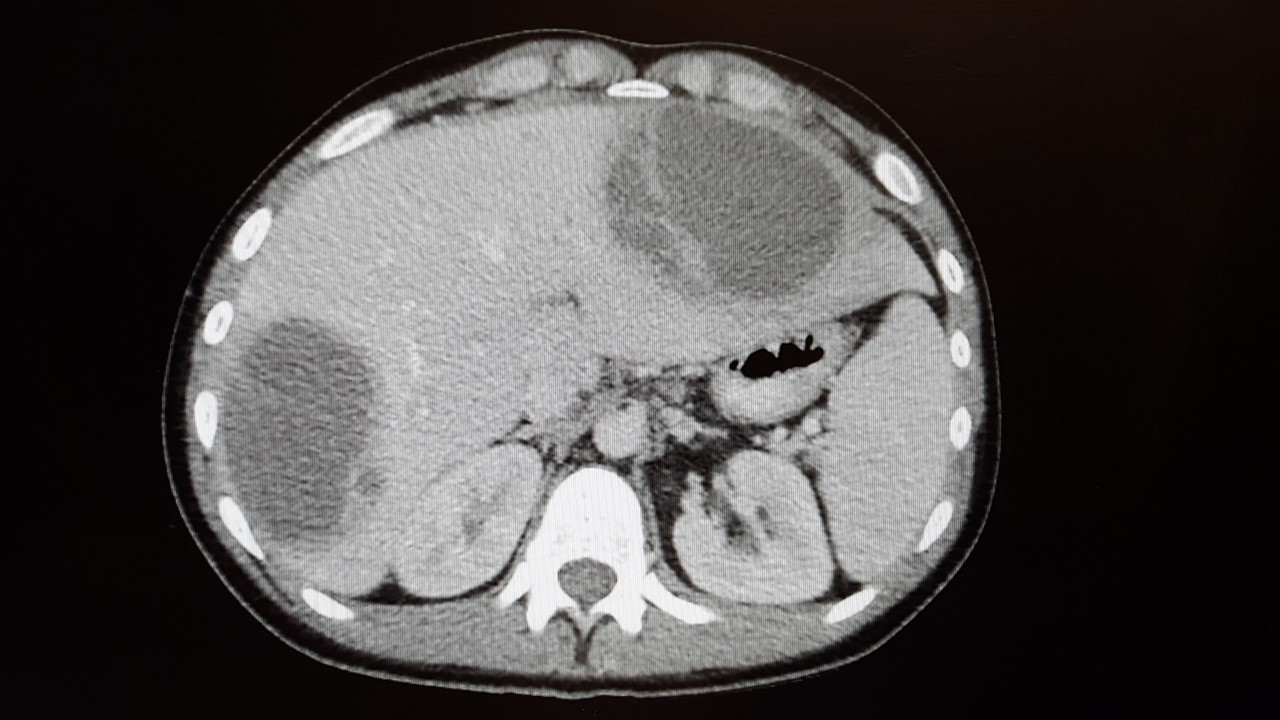

影像學檢查通常建議做腹部超音波檢查及電腦斷層檢查。電腦斷層對於肝膿瘍有很好的敏感性95% 而且可以同時評估是否有合併其他的腹內感染。

但是當電腦斷層無法確定是細菌性肝膿瘍或是阿米巴肝膿瘍。核磁共振也可以協助評估是否為肝膿瘍,但是使用的機會相對低。